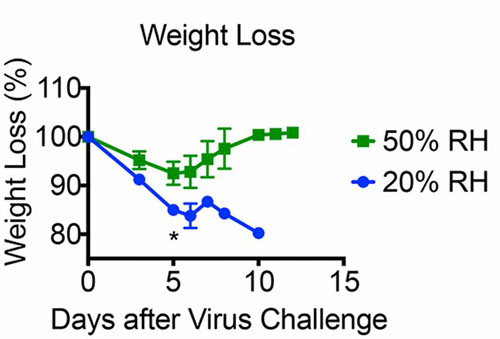

The study found that mice housed at 20%RH suffered a worse disease course compared to those kept at 50%RH, with more rapid and greater weight loss, drop in body temperature and shortened survival. In fact, whereas all mice at the lower humidity died within 11 days of infection, of those that experienced 50%RH, just under half survived until the end of the experiment.